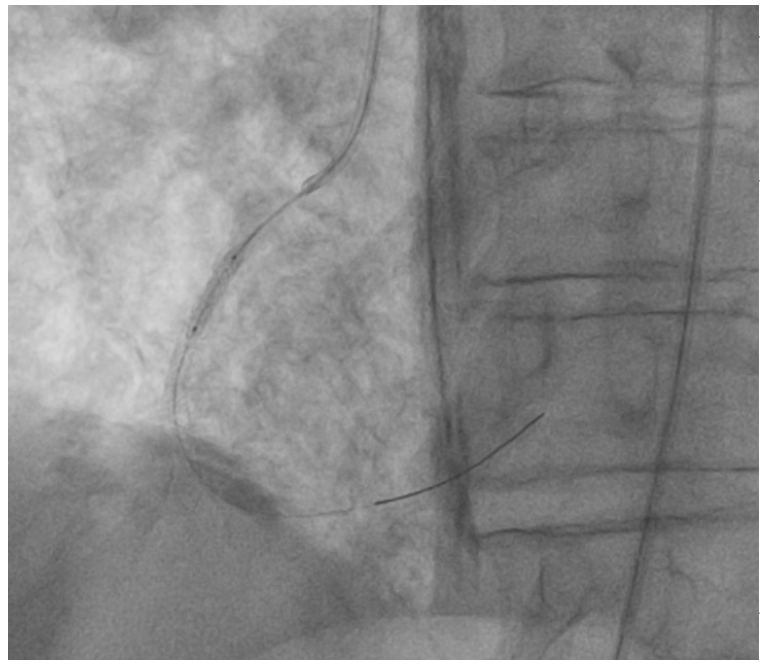

A 67-year-old male presented with non-ST-elevation myocardial infarction (STEMI). Angiography showed severe restenosis within the previously (before 2 years) implanted 2 stents (3 x 24 mm) in the right coronary artery (RCA). Severe calcification was evident angiographically (Figure 1) and after multiple dilations with noncompliant (NC) balloons, the focal underexpansion of the stent remained (Figure 2). This was confirmed by intravascular ultrasound with a minimum stent area (MSA) of 1.98 mm2 (Figure 3). A 3 x 12 mm intravascular lithotripsy (IVL) balloon was used and after the third series of 10 pulses, full expansion of the stent was observed (Figure 4). Postdilation of stenosis with NC and drug-eluting balloons was accompanied by excellent angiographical result with residual stenosis 0%, Thrombolysis in Myocardial Infarction 3 flow, and MSA of 6.4 mm2. The patient was discharged free of symptoms and remains uneventful with no complications. The case demonstrates the feasibility of IVL in acute coronary syndromes related to stent underexpansion due to severe calcification that is refractory to other conventional techniques.